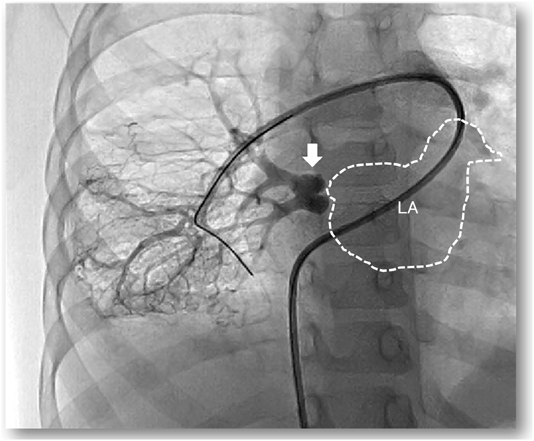

Fig. 1 Contrast-enhanced computed tomography (CT) in case 1

CT demonstrated a hypoplastic right lung. The right pulmonary artery is depicted (black arrow) while the right pulmonary vein is not visualized (white arrow).